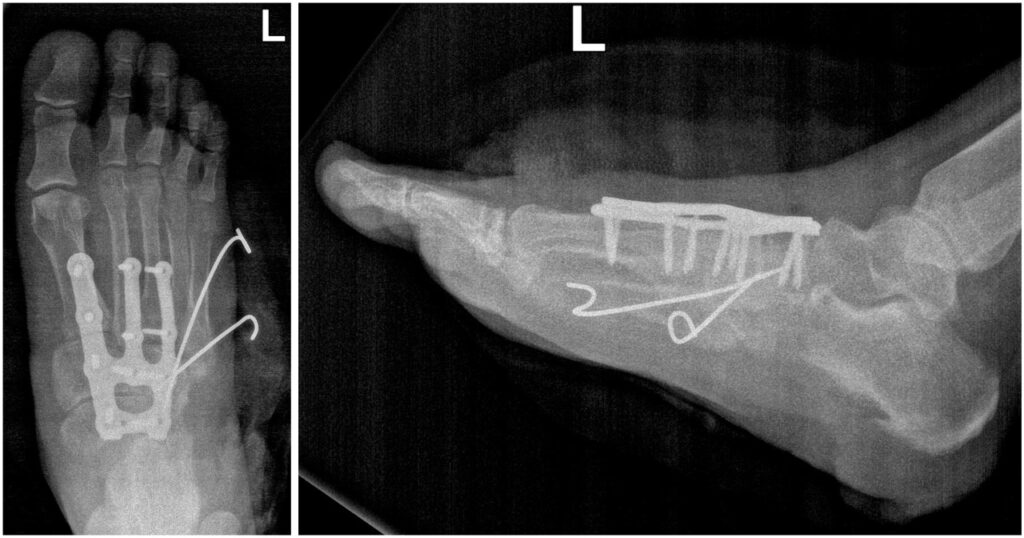

Подготовка к операции включала несколько этапов. Сначала специалисты создали точную виртуальную и физическую 3D-модель стопы пациента на основе данных компьютерной томографии. Затем — предоперационное планирование: врачи детально отработали план коррекции деформации на специальной модели и определили оптимальную конфигурацию будущей конструкции.

Далее непосредственно изготовление имплантата — для фиксации была спроектирована и напечатана индивидуальная титановая пластина, идеально соответствующая анатомии пациента после реконструкции.

«Суть вмешательства заключалась в точной реконструкции сустава Лисфранка. В ходе операции мы восстановили естественное соотношение костей стопы и зафиксировали его с помощью индивидуальной титановой пластины, вернув стопе её опорную функцию.

Аддитивные технологии в нашем институте — это уже не экзотика, а стандарт работы со сложными случаями в хирургии стопы и голеностопного сустава. Мы используем их при застарелых деформациях и в ситуациях, требующих уникальных решений, где стандартные методы могут оказаться недостаточно эффективными. Этот подход позволяет нам с уверенностью браться за лечение самых сложных пациентов», — добавляет Сергей Михайлович.